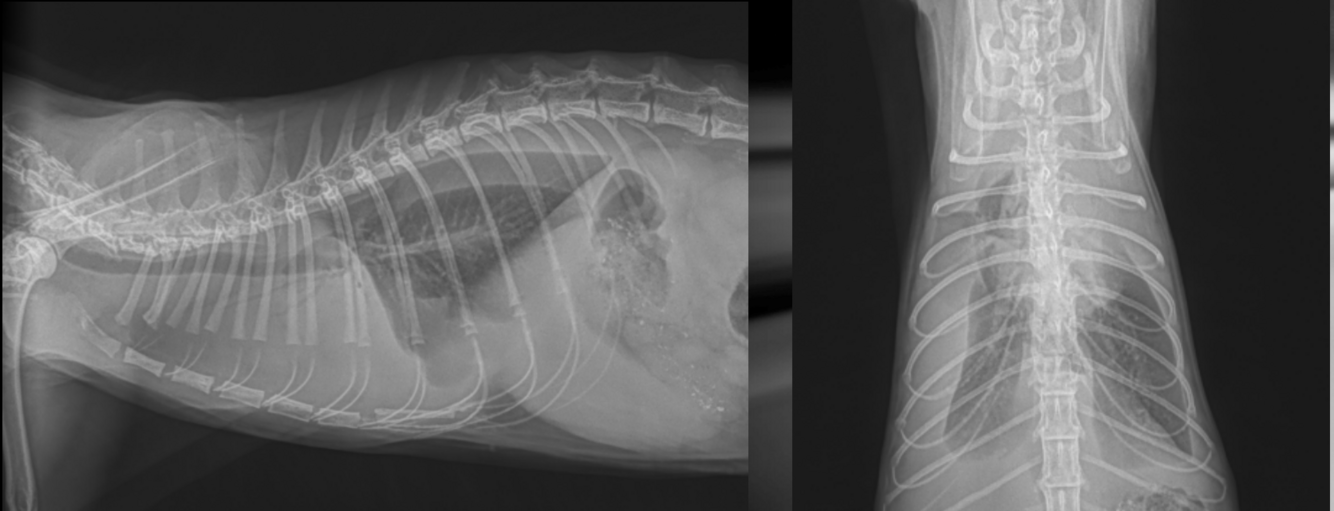

What is shown in these images?

segmented megaesophagus due to vascular ring anomaly/persistent right aortic arch

segmented megaesophagus: -top: food stuck in esophagus -bottom: focal dilatation cranial to heart as seen w/ contrast media